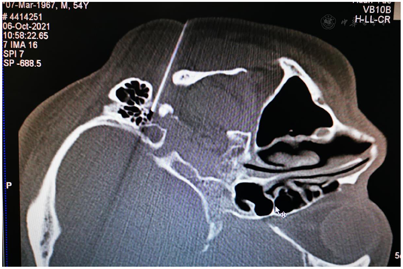

入院后完善相关检查:血常规、尿常规、血沉、凝血全套、前降钙素、梅毒系列+HCV+HIV 、乙肝三系+梅毒系列+HCV+HIV、大便常规+OB、生化分析、肿瘤相关物质测定、肿瘤系列均未见明显异常;术前头颅CT、颅脑MR检查排除了桥脑-小脑角占位病变,使用三维飞行时间磁共振血管造影(3D-TOF MRA)未见双侧面神经根遭受伴行血管压迫(图1)。术前面部表面肌电图可见双侧眼轮匝肌同步收缩和口轮匝肌爆发性放电,未见异常肌电反应(abnormal muscle response,AMR)。

鉴于MS与HFS的临床表现有高度相似之处,我们设想,用于治疗HFS的面神经射频技术有望用治疗MS。经报请医院伦理委员会讨论通过(LS2019-013),决定给患者施行双侧面神经射频治疗。术前向患者及其家属详细交待操作经过和可能出现的轻度面神经麻痹并发症,取得知情同意并签署书面知情同意书后,嘱患者右侧向上侧卧于CT台上,安置血压、心电图、脉搏血氧饱和度监测设施并给予鼻导管吸氧,并在耳垂前后放置CT定位定位栅(图2)。用鼻旁窦模式拍摄头颅定位像,并对乳突区进行层厚3 mm轴位扫描,选取含茎乳孔且无颞骨鼓部骨质阻挡的CT层面作为穿刺层面,并在该层面上设计穿刺路径:以右侧茎乳孔为穿刺靶点,用CT自带测量工具软件由右茎乳孔向前上拉直线,该线与皮肤的交点即为穿刺点,测量穿刺深度(穿刺点至靶点的距离)和穿刺角度(穿刺路线与矢状面的夹角)(图3)。对穿刺点进行局部麻醉,用长度为10 cm、裸露端为5 mm的7号射频针在CT引导下穿刺至靶点(图4)并CT扫描三维重建观察确认(图5),随后用低频(2 Hz)电流进行运动神经刺激测试,0.5 mA电流电刺激即能诱发出右侧面肌出现与电刺激相同频率痉挛性抽动,见视频,给予65℃标准射频消融,同时嘱患者鼓腮、闭眼,射频第27秒鼓腮漏气,右眼不能紧闭,即停止射频,结束手术,见视频。2 d后同样于CT引导下行左侧茎乳孔穿刺面神经射频消融治疗(图6,图7,图8)。